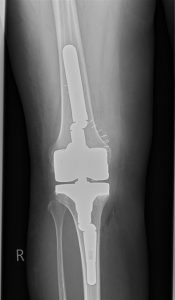

(Bild rechts: Austausch durch eine stabilisierte Revisionsendoprothese. Die Beinachse ist nun gerade, das Kniegelenk auch bei Belastung stabil.)